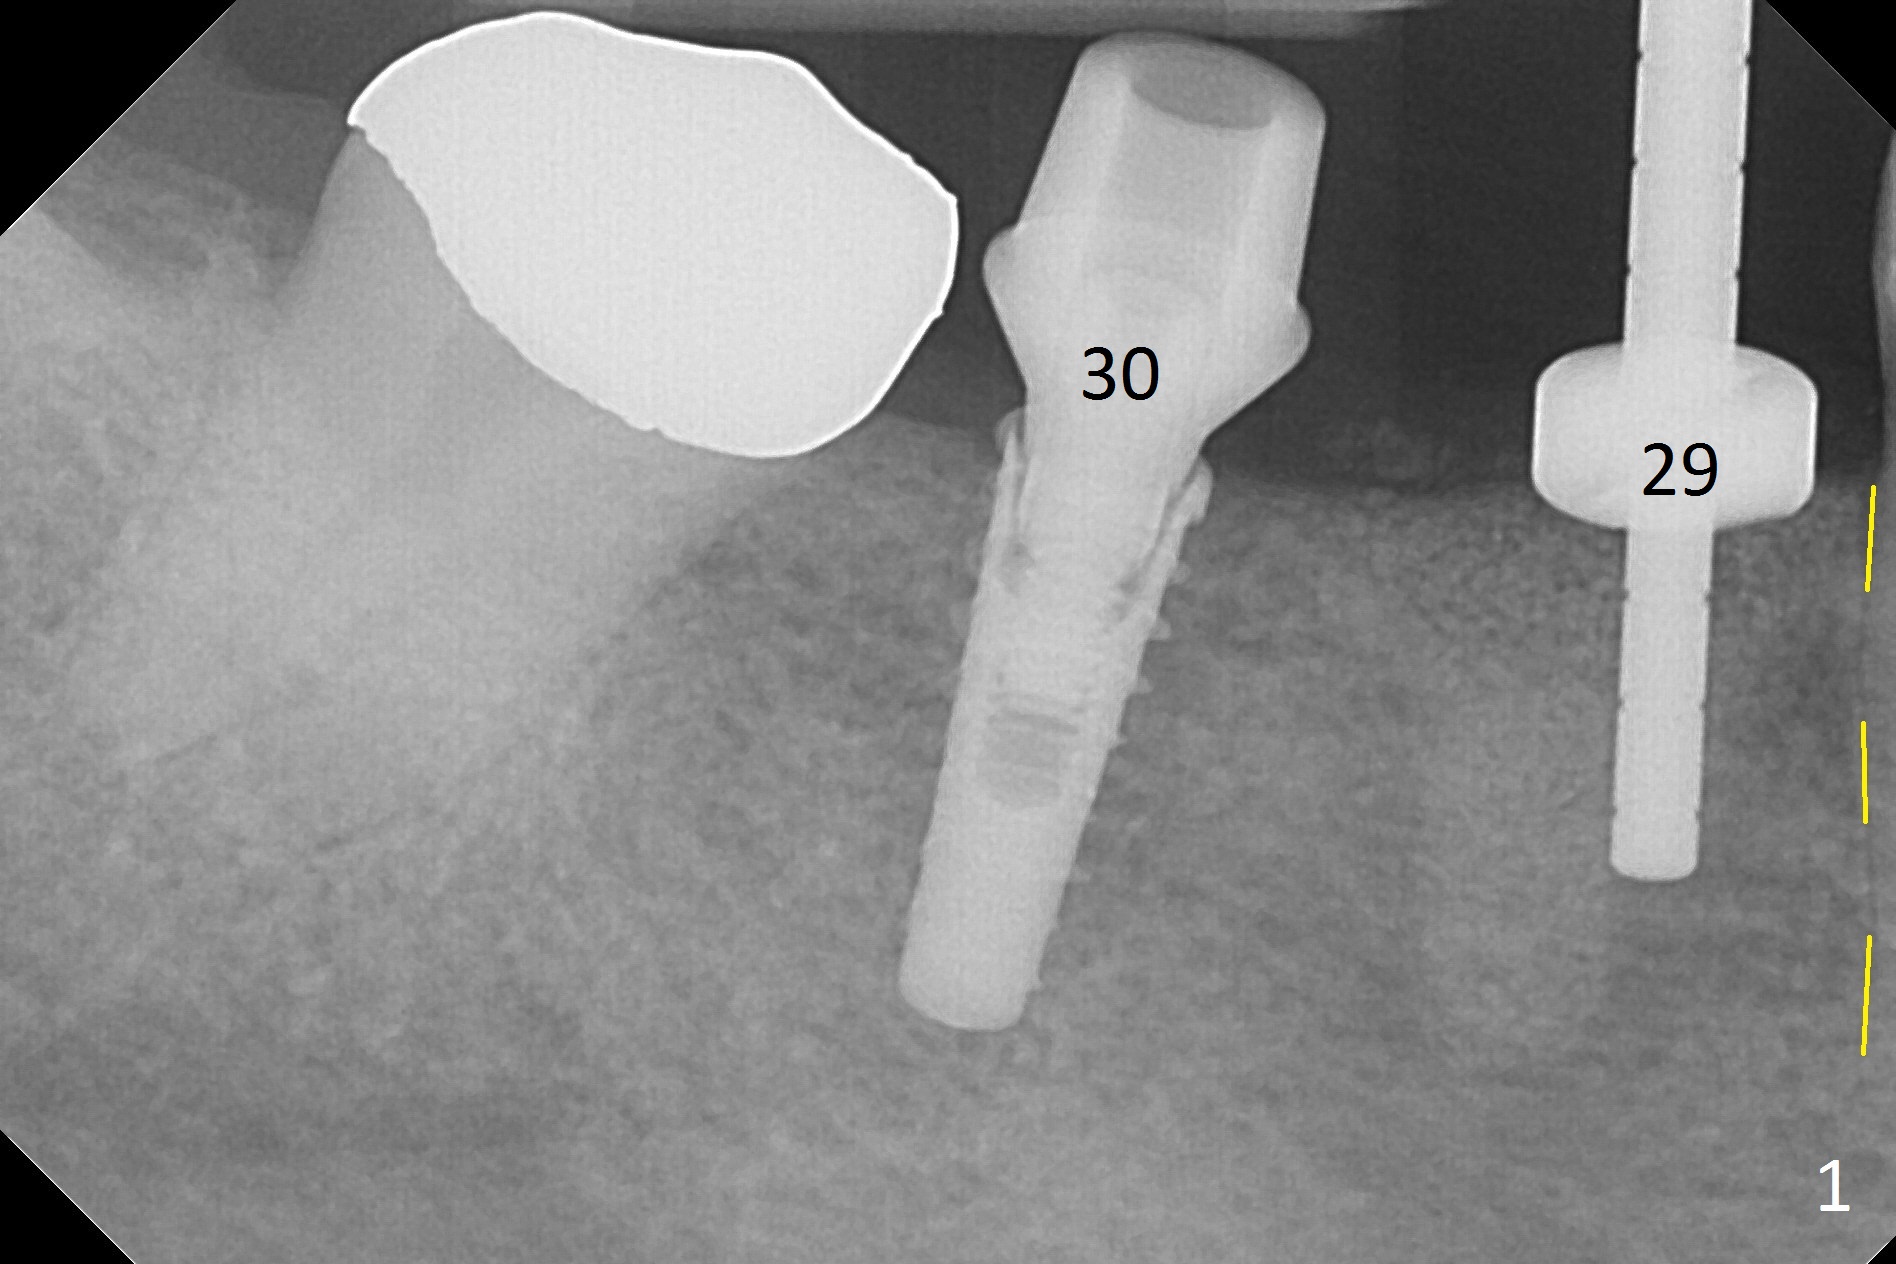

After incision, the ridge at #29 and 30 is found ~ 5 mm wide buccolingually. To place a 4x11 mm IBS implant at #30, the ridge is expanded using BEB technique (bone expansion and bending, Fig.1). It appears that the initial osteotomy at #29 is mesial (Fig.1 yellow dashed line: the distal surface of the root of the tooth #28). After moving the osteotomy distal, the final implant position at #29 (4x11 mm) is within normal limit (Fig.2). The bone at #29 seems to be not so dense that bending (using 1.6 mm drill) is not necessary (using Magic Split and Magic Expanders 3 and 3.8 mm). Later the implant at #30 (4x11 mm) is placed deeper (Fig.3). After placing bone graft around the implants/abutments and suturing, the ridge looks wider with apparent formation of the gingival bands around the abutments (Fig.4 *). Three months and a half postop, bone loss is minimal (Fig.5) and gingival bands forms around the abutments (Fig.6). Fig.7 is taken 1 month post cementation (panoramic X-ray). The patient chews normally 1 year (Fig.8) and nearly 2 years (Fig.9,10) post cementation. The crown at #31 needs recementation 2 years 7 months post #30 cementation; the incomplete seating of the abutment was noted for the first time (Fig.11). Five months later the patient is going to be retired and wants to travel abroad. After approval, the access hole was reopened; articulating paper shows under occlusion of the crown (Fig.12). Since the gap between the abutment and the implant is large, the abutment/crown complex seems to be necessary to be turned (Fig.13 curved arrow). The proximal surfaces of the crown need to be trimmed (straight lines). After turning, the crown sits down with screw tightening; the patient feels pain from the gingival cuff (Fig.14). After turning, the abutment appears to be completely seated (Fig.15). In fact the mesial and distal surfaces of the crown should have clearance from the neighboring teeth (Fig.14) so that pick-up impression is able to hold the crown/abutment complex securely (Fig.16: *). The crown is separated from the abutment after crown repair. They are seated together (loose connection) using the crown as a guide to seat the abutment. BW is taken without the crown. It appears that the abutment remains seated completely (Fig.17). The apical space is equal between #29 and 30 (Fig.17, as compared to Fig.5).